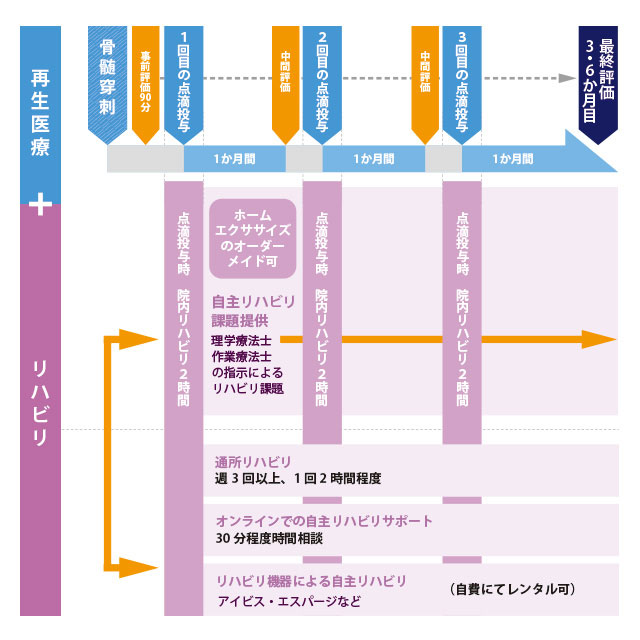

「同時リハビリ×再生医療™」治療プラン

当クリニック独自の「同時リハビリ×再生医療™」の特長の一つは、磁気刺激装置、電気刺激装置、ロボットなどテクノロジーを活用したリハビリを行うことです。

これらのデバイスによる脳や神経への刺激は、損傷部位の血流を増加させ、修復を助ける一方で、運動神経と感覚神経の神経回路を効率的に鍛えます。また、リハビリの過程では、定期的に身体機能の評価をすることも大切です。スタート時点からどれだけ改善しているか、記録して推移を確認しています。

「同時リハビリ×再生医療™」治療プランの流れ